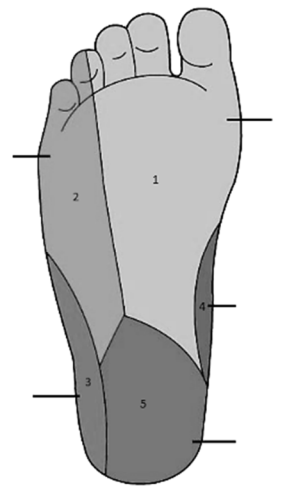

Um paciente de 44 anos de idade tentou suicídio atirando-se na frente de um ônibus. O motorista desviou-se, mas a perna esquerda do paciente foi atropelada, com fraturas múltiplas de tíbia e fíbula, manejadas com uso de fixador externo. O paciente atualmente se queixa de insensibilidade nas zonas 3 e 4, representadas na figura. Quais nervos devem ter sido afetados, respectivamente?